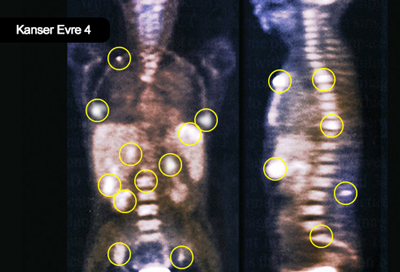

Evreler

• Evre 1: Başka bir yere yayılmayan tek tümör

• Evre 2: Damar içine yayılan bir tümör veya birden fazla tümör, ancak tümör çapı 5 cm-nin altında olması

• Evre 3: Büyük damarlara ve komşu organlara yayılan bir tümör veya birden fazla tümör veya bu tümörlerden birinin çapının 5 cm-den büyük olması

• Evre 4: Kanserin diğer organlara yayılması